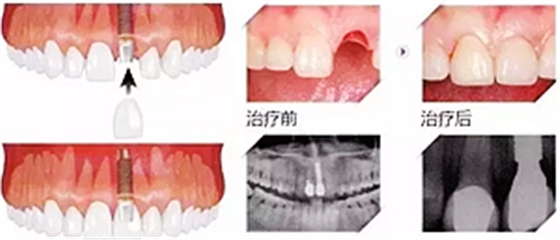

7、大幾千甚至過萬的種植牙

當牙齒最終齲壞到只剩殘根,只能拔除,拔牙雖然不貴,但是拔牙之后的鑲牙并不便宜,目前比較好的鑲牙方式種植牙,一般要大幾千甚至過萬元一顆。這個價格對于普通人來說算很貴了。但沒辦法,誰叫你一拖再拖呢,快趁有人工補救的機會種上吧,有些人想種牙還受身體條件限制種不了呢。

那你要說如果壞牙直接拔掉,不鑲牙不就好了?那我只能說No zuo No die!時間久了,兩邊的牙向缺牙的地方倒了,對應(yīng)的咬合面上的牙齒伸長了,這時候會發(fā)現(xiàn)缺牙附近前后左右的牙吃東西都塞牙,長期的塞牙造成其他牙齒的齲壞,開始了上述的循環(huán)。